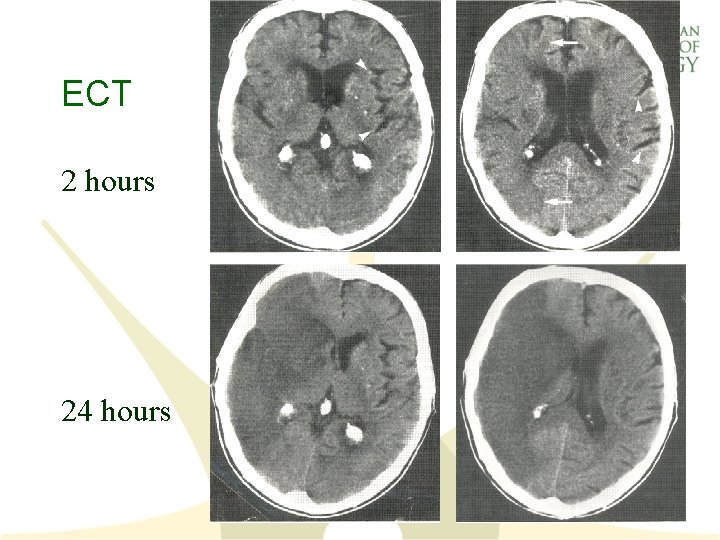

Non-contrast CT of the Head • Initial imaging study of choice • Readily available • Very sensitive for blood in the acute phase – blood - 50 -85 Hounsfield Units – bone- 120 (70 -200) Hounsfield Units • Not sensitive for acute ischemic stroke – nearly 100% sensitive by 7 days • Posterior fossa structures - bone artifact

Non-contrast CT of the Head • May shows early signs of ischemia in the 1 st 3 hours – loss of gray/white matter distinction – hypodensity – mass effect, edema – hyperdense middle cerebral artery sign • Re-evaluate the time of symptom onset, if early signs of ischemia are present

ECT 2 hours 24 hours